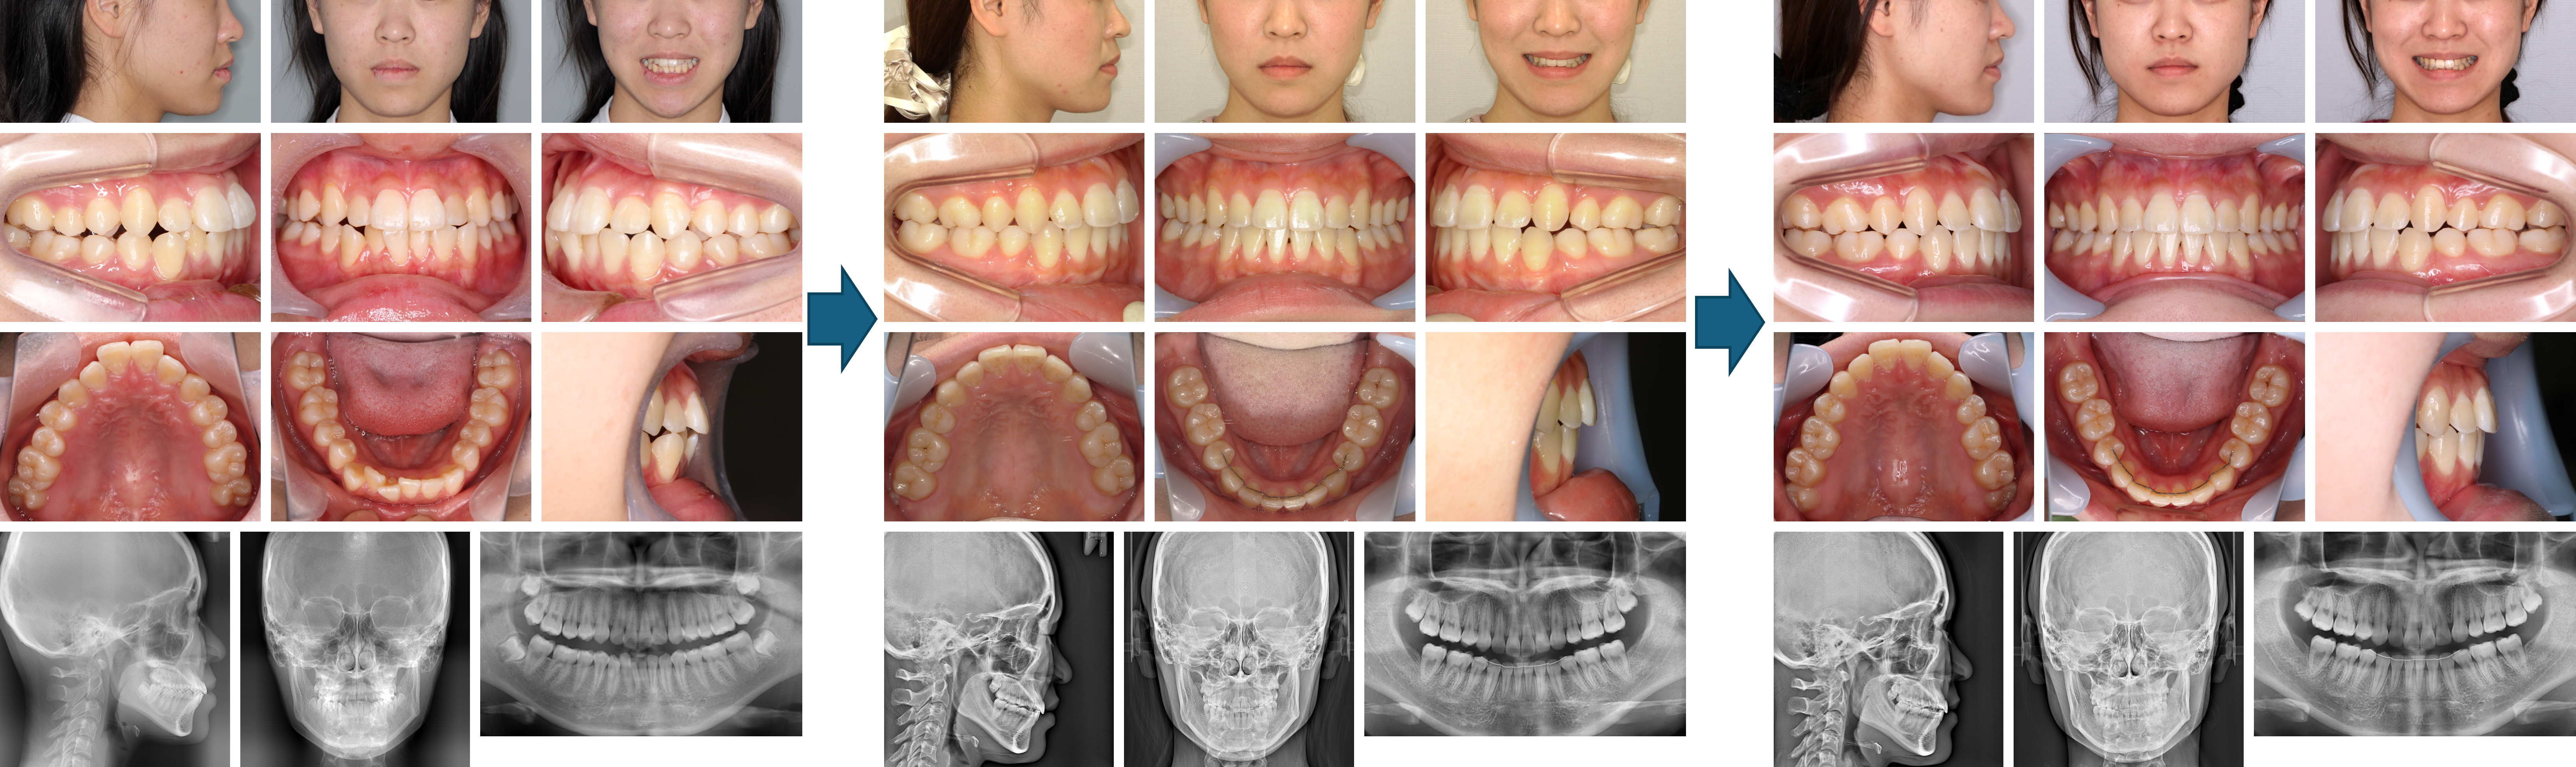

【治療例 K5102】初診時年齢:8歳2か月 / 性別:女性 / 主訴:上の前歯が出ている

治療の概要:下顎骨が後退した著しい上顎前突症例でした。第1期治療では、下顎骨の前方誘導は図るために上顎に咬合斜面板を装着しました。その後、上顎に2×4装置とヘッドギアで上顎骨の成長抑制を図りました。第2期治療では残りの永久歯にマルチブラケット装置を装着しました。その結果、綺麗な側貌と緊密な咬合を獲得できました。

主訴: 上の前歯が出ている

診断名: 上顎中切歯の著しい唇側傾斜を伴う上顎前突

使用した主な装置: サービカルヘッドギア、咬合挙上板、マルチブラケット装置、顎間ゴム

抜歯/非抜歯および抜歯部位: 非抜歯(ただし、乳歯の抜歯はあり)

治療期間:4年7か月

治療回数:66回

【治療例 K7719】初診時年齢:12歳1か月 / 性別:男性 / 主訴:出っ歯で口が閉じにくい

症例の概要:主訴は出っ歯で口が閉じにくい。サービカルヘッドギアと2×4装置にて上顎骨の成長抑制、下顎の成長促進を行った。さらにマルチブラケット装置にて緊密な咬合を獲得し、好ましい側貌を得ることが出来た。

主訴: 出っ歯で口が閉じにくい

診断名: 上顎前歯が唇側傾斜した上顎前突症例

使用した主な装置: マルチブラケット装置、サービカルヘットギア、歯肉切除

抜歯/非抜歯および抜歯部位: 非抜歯

治療期間:2年5か月

治療回数:25回